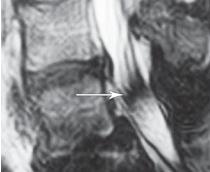

МРТ № 45

На МРТ № 45 наблюдается выраженный эпидурит.